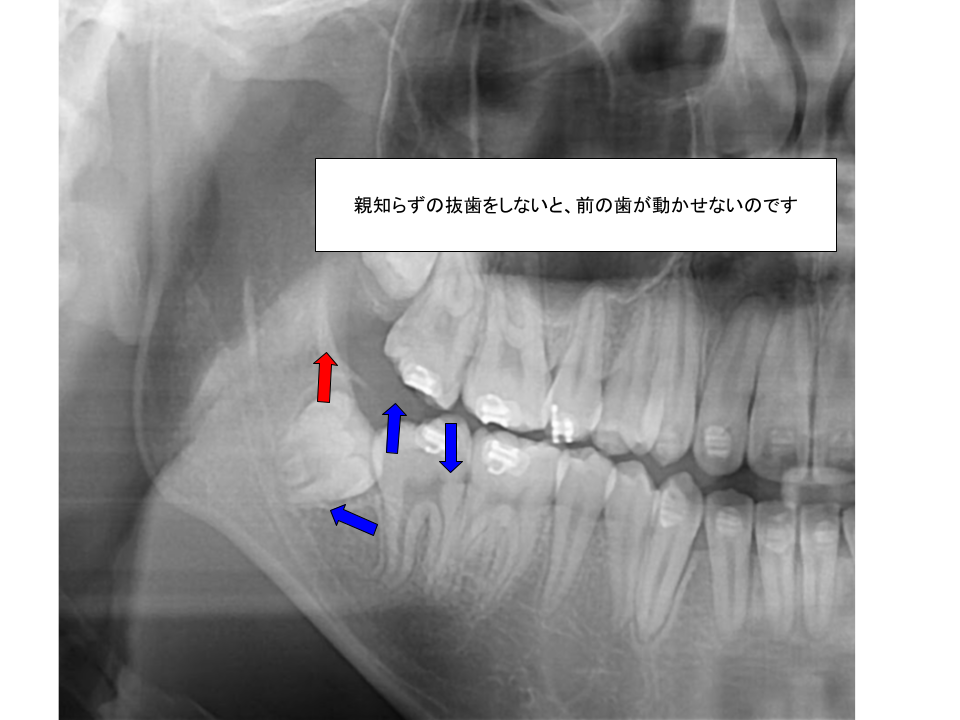

3、歯並びを治す場合

歯列矯正治療を行う際、奥歯の移動が必要となるケースは少なくありません。その際、親知らずが歯の移動の妨げになることがあります。特に、当院で採用しているゴムメタル矯正では、下顎が後退している症例の場合、下顎の親知らずの抜歯は必須となります。

また、親知らずを抜かずに矯正治療を行った場合、矯正終了後に親知らずを抜くべきかどうかは、長年議論されてきました。歯列の安定性を考慮すると、多くの場合、抜歯しておいた方が良いでしょう。